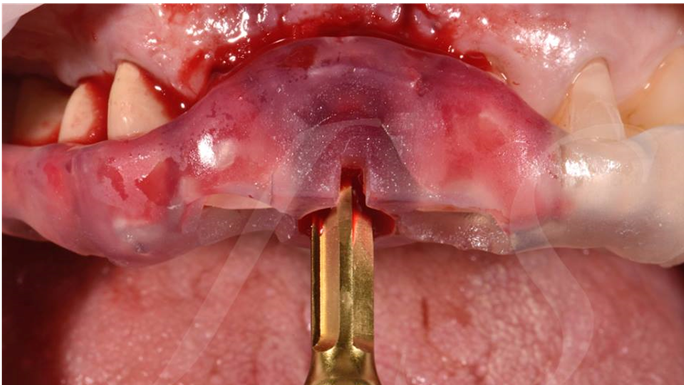

Clinical case: EImmediate implant placement & loading of #35 extraction socket with defect

Dr. Kwang Bum Park, immediate loading, digital guided surgery, digital ONE-DAY implant, maxillary anterior, #21, guided surgery, immediate loading, AnyRidge, R2GATE, Mega ISQ, MEG Torq, R2GATE Full Surgical Kit

implant system, R2GATE Guide, R2GATE surgical kit (AnyRidge), Mega ISQ, Mega-Oss

“ One implant /One tooth/ One hour step-by-step

+ associated connective graft ”